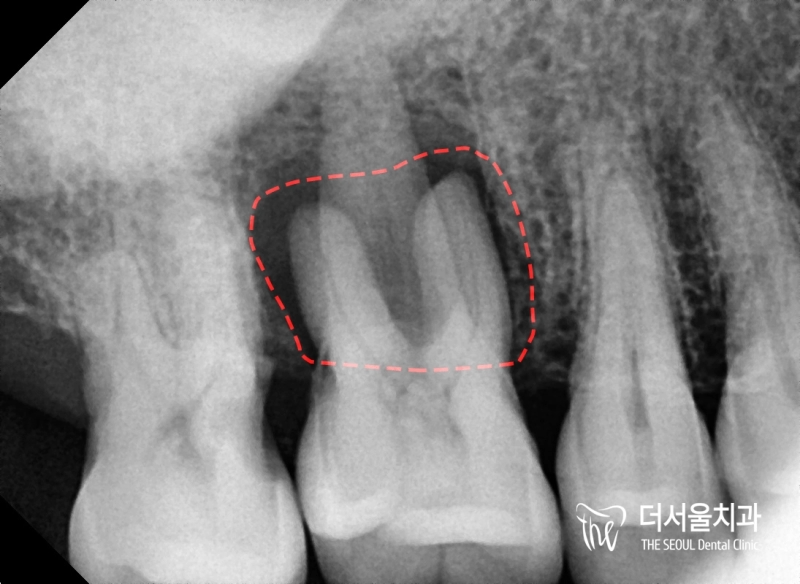

반갑습니다. 수진동 더서울 치과 입니다. 항상 느끼고 있는 거지만, 구강 관리는 꾸준히 이어나가신다면 건강히 잘 유지할 수 있다는 점입니다.